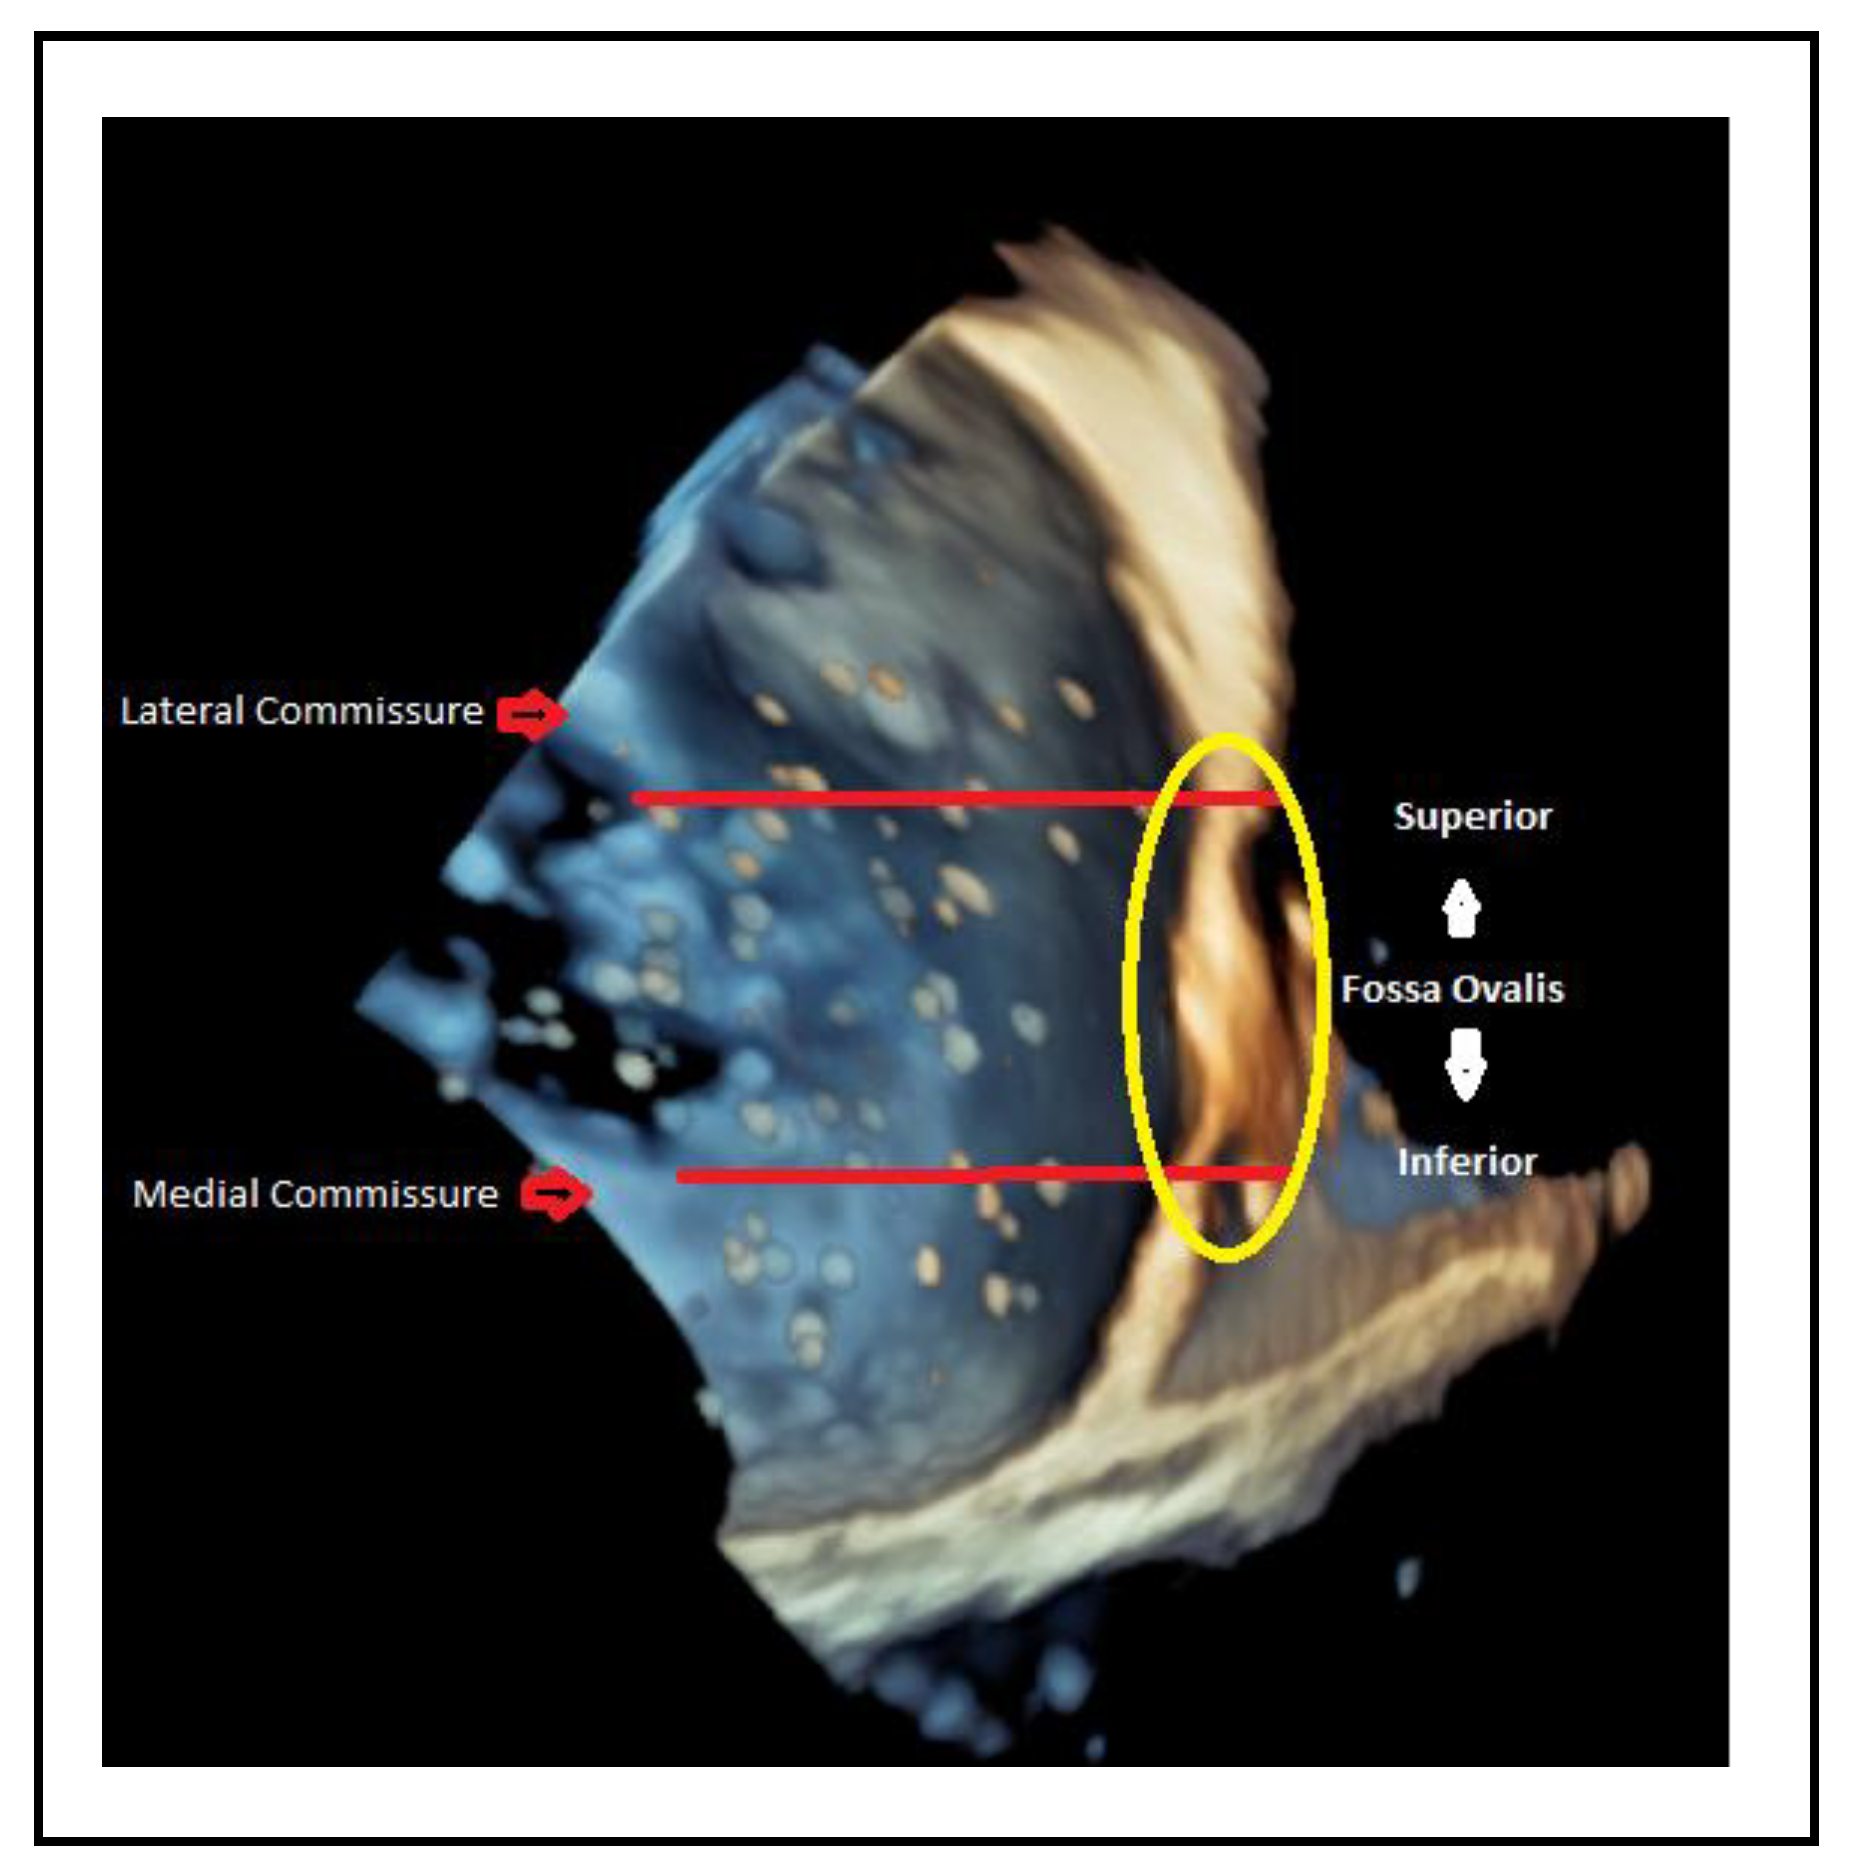

- Lateral commissure: A superior and lower puncture height, approximately 3.5 cm, is preferred to facilitate access.[40]

- Medial commissure: A more inferior puncture, closer to the inferior vena cava (IVC), with a higher height of 4.5–5 cm is recommended for better alignment. [41]

- Ventricular functional MR: The puncture height should be set 1 cm lower than the usual height to match the coaptation depth.[40]